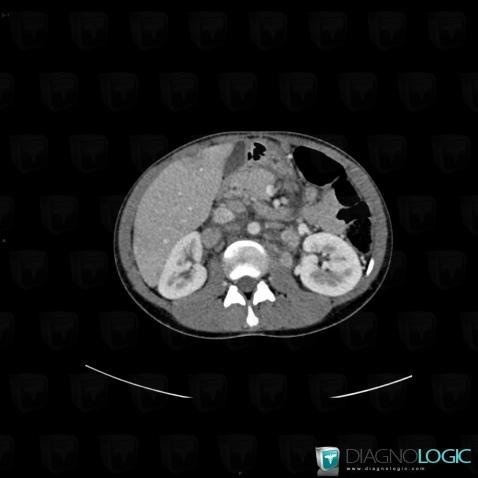

Sarcoïdose, Rétroperitoine, Scanner

Voici les informations spécifiques à l'image clé ci dessus:

- Diagnostic Sarcoïdose, Localisation(s) Rétroperitoine, comportant les gammes Adénopathie rétropéritonéale, Masse rétropéritonéale hypodense